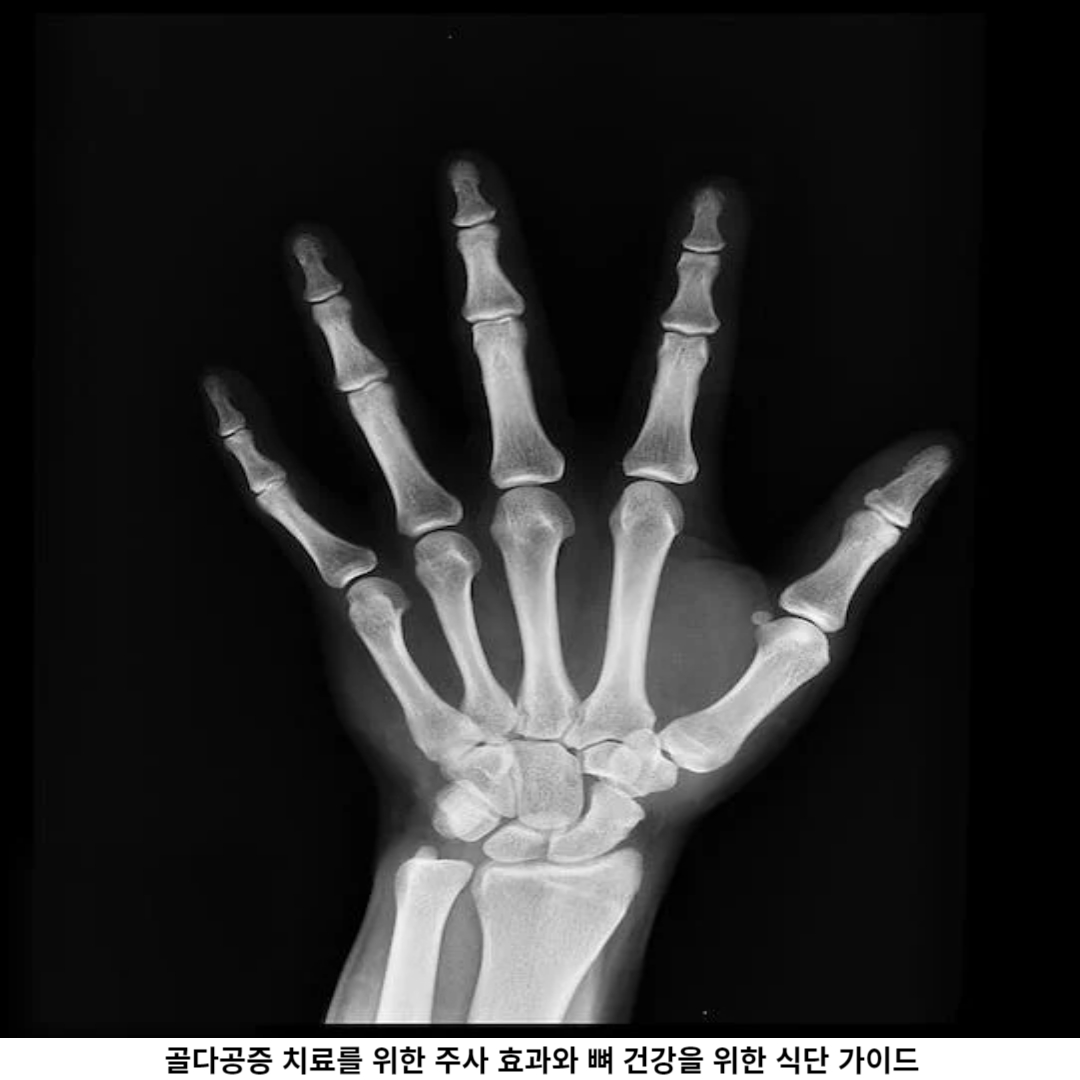

골다공증의 증상으로는 허리 통증, 등과 목의 굽은 자세, 키의 감소, 무게 중심의 변화, 골절 등이 있습니다. 하지만 초기에는 특별한 증상이 없을 수도 있으므로 매년 정기적인 검진과 뼈 밀도 측정을 통해 확인하는 것이 중요합니다.

2. 골다공증의 치료 방법

골다공증의 치료 방법은 약물 치료와 운동 요법과 병행합니다. 약물 치료는 뼈 손실을 최대한 줄이고 새로운 뼈 형성을 촉진하기 위해 사용됩니다.

주로 사용되는 약물로는 비스포스포네이트, 셀레 크심, 확산체 억제제 등이 있으며, 이들은 서로 각자 다른 작용 원리를 가지고 있습니다.